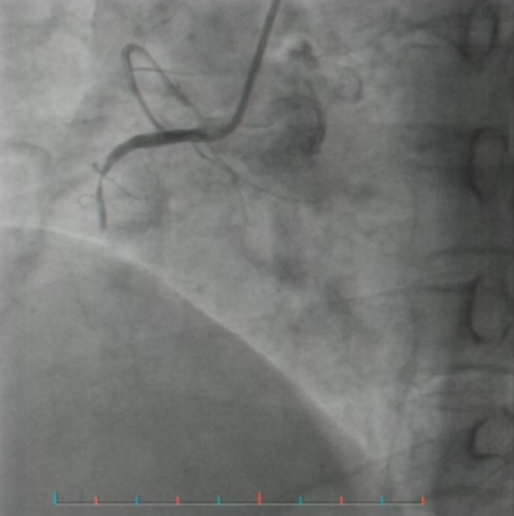

第二天,她前往湖南省中西医结合医院(湖南省中医药研究院附属医院)就诊,心电图结果令人震惊:急性心肌梗死。心血管内三科陆胜主任医师团队迅速为她进行冠脉造影并开通堵塞血管。手术成功,彭阿姨转危为安。

(▲造影示血管闭塞)